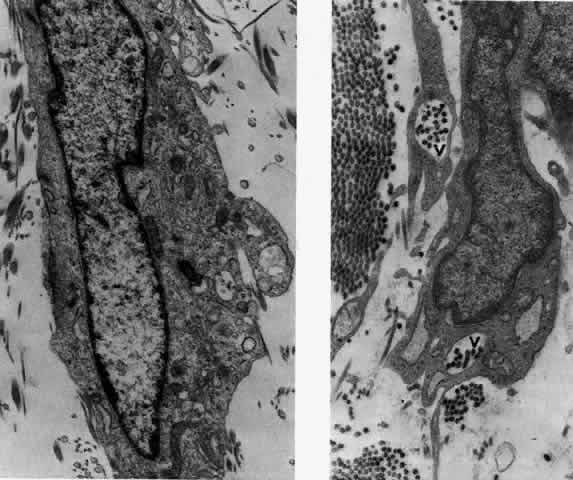

Fig. 23. Electron micrographs of scleral stroma at the periphery of an area of ulceration

in a patient with necrotizing scleritis. The left shows an active

fibroblastic cell, and the right shows collagen fibrils within intracellular

vacuoles (V) in the fibroblastic cell. (Left X15,375; right

X15,375) (Watson PG, Young RD: Changes at the periphery of a lesion necrotizing

scleritis: Anterior segment fluorescein angiography correlated with electron

microscopy. Br J Ophthalmol 68:781–789, 1984) Fig. 23. Electron micrographs of scleral stroma at the periphery of an area of ulceration

in a patient with necrotizing scleritis. The left shows an active

fibroblastic cell, and the right shows collagen fibrils within intracellular

vacuoles (V) in the fibroblastic cell. (Left X15,375; right

X15,375) (Watson PG, Young RD: Changes at the periphery of a lesion necrotizing

scleritis: Anterior segment fluorescein angiography correlated with electron

microscopy. Br J Ophthalmol 68:781–789, 1984)

|